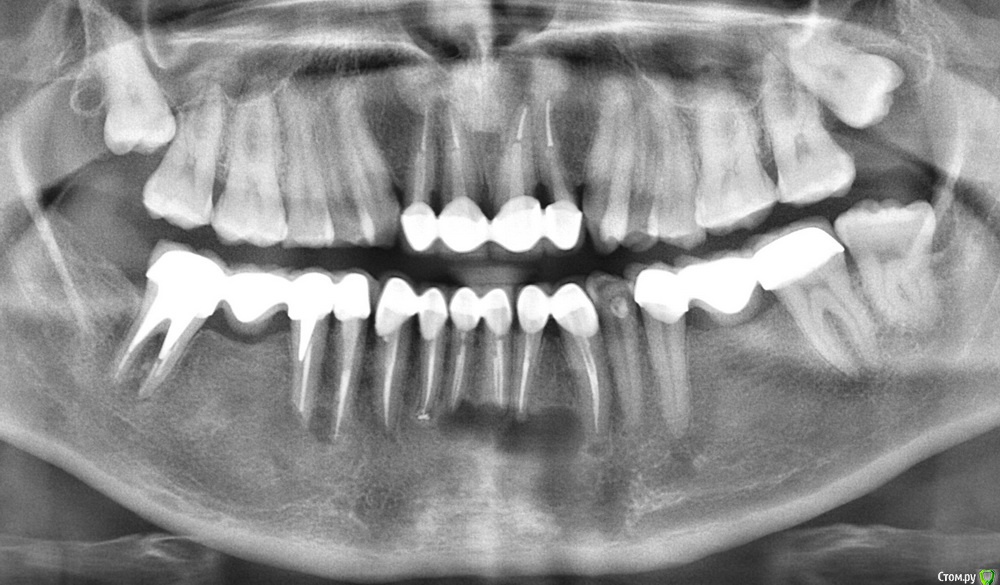

edvard Опубликовано 11 мая, 2011 Поделиться Опубликовано 11 мая, 2011 (изменено) Страшно смотреть стало на улыбку в зеркале, пытаюсь перебороть зубную фобию и решил заняться зубами. Стерлись все передние резцы. Процесс истирания длился наверно года 3. До этого прикус был в норме.Мне 35 лет. Язва 12-ти перстной кишки присутствует. Возможно ночами бруксизмом занимался от периодических ночных болей в животе. Сегодня был на приёме в стоматологии, вынесли вердикт: - нижняя челюсть : всё депульпировать, перепломбировать и под металлокерамику. - верхняя челюсть : четыре центральных зуба депульпировать и то же в коронки. Подскажите пожалуйста , правильно ли выбран план лечения в данной ситуации. Очень страшно депульпировать сразу 9 зубов. И сомнения вызывает собственно сама необходимость депульпирования. Неужели это действительно необходимо делать при живых зубах и при условии что за счёт металлокерамики будет выставляться правильный прикус. Спасибо всем отозвавшимся за ваши мнения. http://s42.radikal.ru/i096/1105/dc/0074cc18379bt.jpg http://i003.radikal.ru/1105/c4/f5507b16fe60t.jpg http://s44.radikal.ru/i106/1105/2d/0d12bba70e11t.jpg http://s010.radikal.ru/i314/1105/f8/d2bf1cc7ea77t.jpg Изменено 11 мая, 2011 пользователем edvard Ссылка на комментарий

Штаматолог Опубликовано 11 мая, 2011 Поделиться Опубликовано 11 мая, 2011 так вот собственно из за решения всё депульпировать у меня и появились сомнения в правильности выбранной методики лечения. из за этого я и тему эту создал, что бы разобраться что к чему. Может есть ещё какие то альтернативные варианты лечения? я так понимаю нужно для начала с прикусом разобраться. брекеты тут уже не помогут. может капы какие то или ещё что то придумано в современной стоматологии ?это я как раз и забыл спросить у ортопеда, т.к. немного в шоке пребывал. осознание пришло позже Депульпировать все под МК нет никакой необходимости. Очень хорошо, что вас это насторожило. МК коронки на 4 верхних резца ситуацию никак не поменяют, ни функционально, ни эстетически. Конкретных планов я лично не возьмусь писать даже с учетом наличия неплохих фото и ОПТГ. Во-первых, здесь немаловажно наличие бюджета и исполнителей ( а то насоветовать можно, да толку...) А во-вторых, ваш случай нужно тщательно планировать, нужно больше диагностической инфы. И поработать над вами в итоге нужно будет практически всем специалистам. Ссылка на комментарий

edvard Опубликовано 25 октября, 2017 Автор Поделиться Опубликовано 25 октября, 2017 полечился блин... прошло почти 4 года после протезирования, сделал снимок и вижу что под нижними резцами образовалась киста: хирург посмотрела и сказала - нужно делать резекцию верхушек корней и удалять кисту.подскажите - после удаления полость в кости обязательно заполнять костным материалом? при благополучном стечении обстоятельств, новая костная ткань образуется вокруг этих зубов и они будут там как родные или шататься будут? Ссылка на комментарий

red_butler Опубликовано 26 октября, 2017 Поделиться Опубликовано 26 октября, 2017 после удаления полость в кости обязательно заполнять костным материалом? не обязательно, но в Вашем случае я бы использовал графт и мембрану.Консервативное лечение не рассматриваете? Ссылка на комментарий

edvard Опубликовано 27 октября, 2017 Автор Поделиться Опубликовано 27 октября, 2017 Консервативное лечение не рассматриваете? Я бы с радостью рассмотрел конечно, но уже стоят металлокерамические мосты, жалко их резать и выбрасывать, на новые денег как бы нет Да и терапевт, который пломбировал каналы уверяет что каналы запломбированы идеально и смысла переделывать их и лечить кисту нет никакого.Я в замешательстве.. я бы использовал графт и мембрану. полез гуглить что это такое Ссылка на комментарий